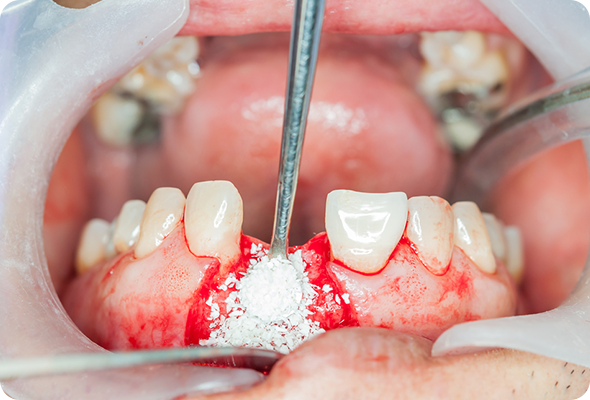

인공뼈의 이식 수술

인공뼈는 가루 형태로 되어 있으며, 단단하게 굳는데 적어도 6개월 이상의 기간이 필요합니다.

이식해야 할 인공뼈의 양이 적은 경우에는 임플란트 수술과 동시에 진행하지만, 양이 많은 경우에는 인공뼈 이식을 먼저 진행하고

추후에 임플란트 수술을 하는 것이 안전합니다.

STEP 03

상악동 빈 공간 사이로

인공뼈를 이식하고,

임플란트를 식립합니다. -